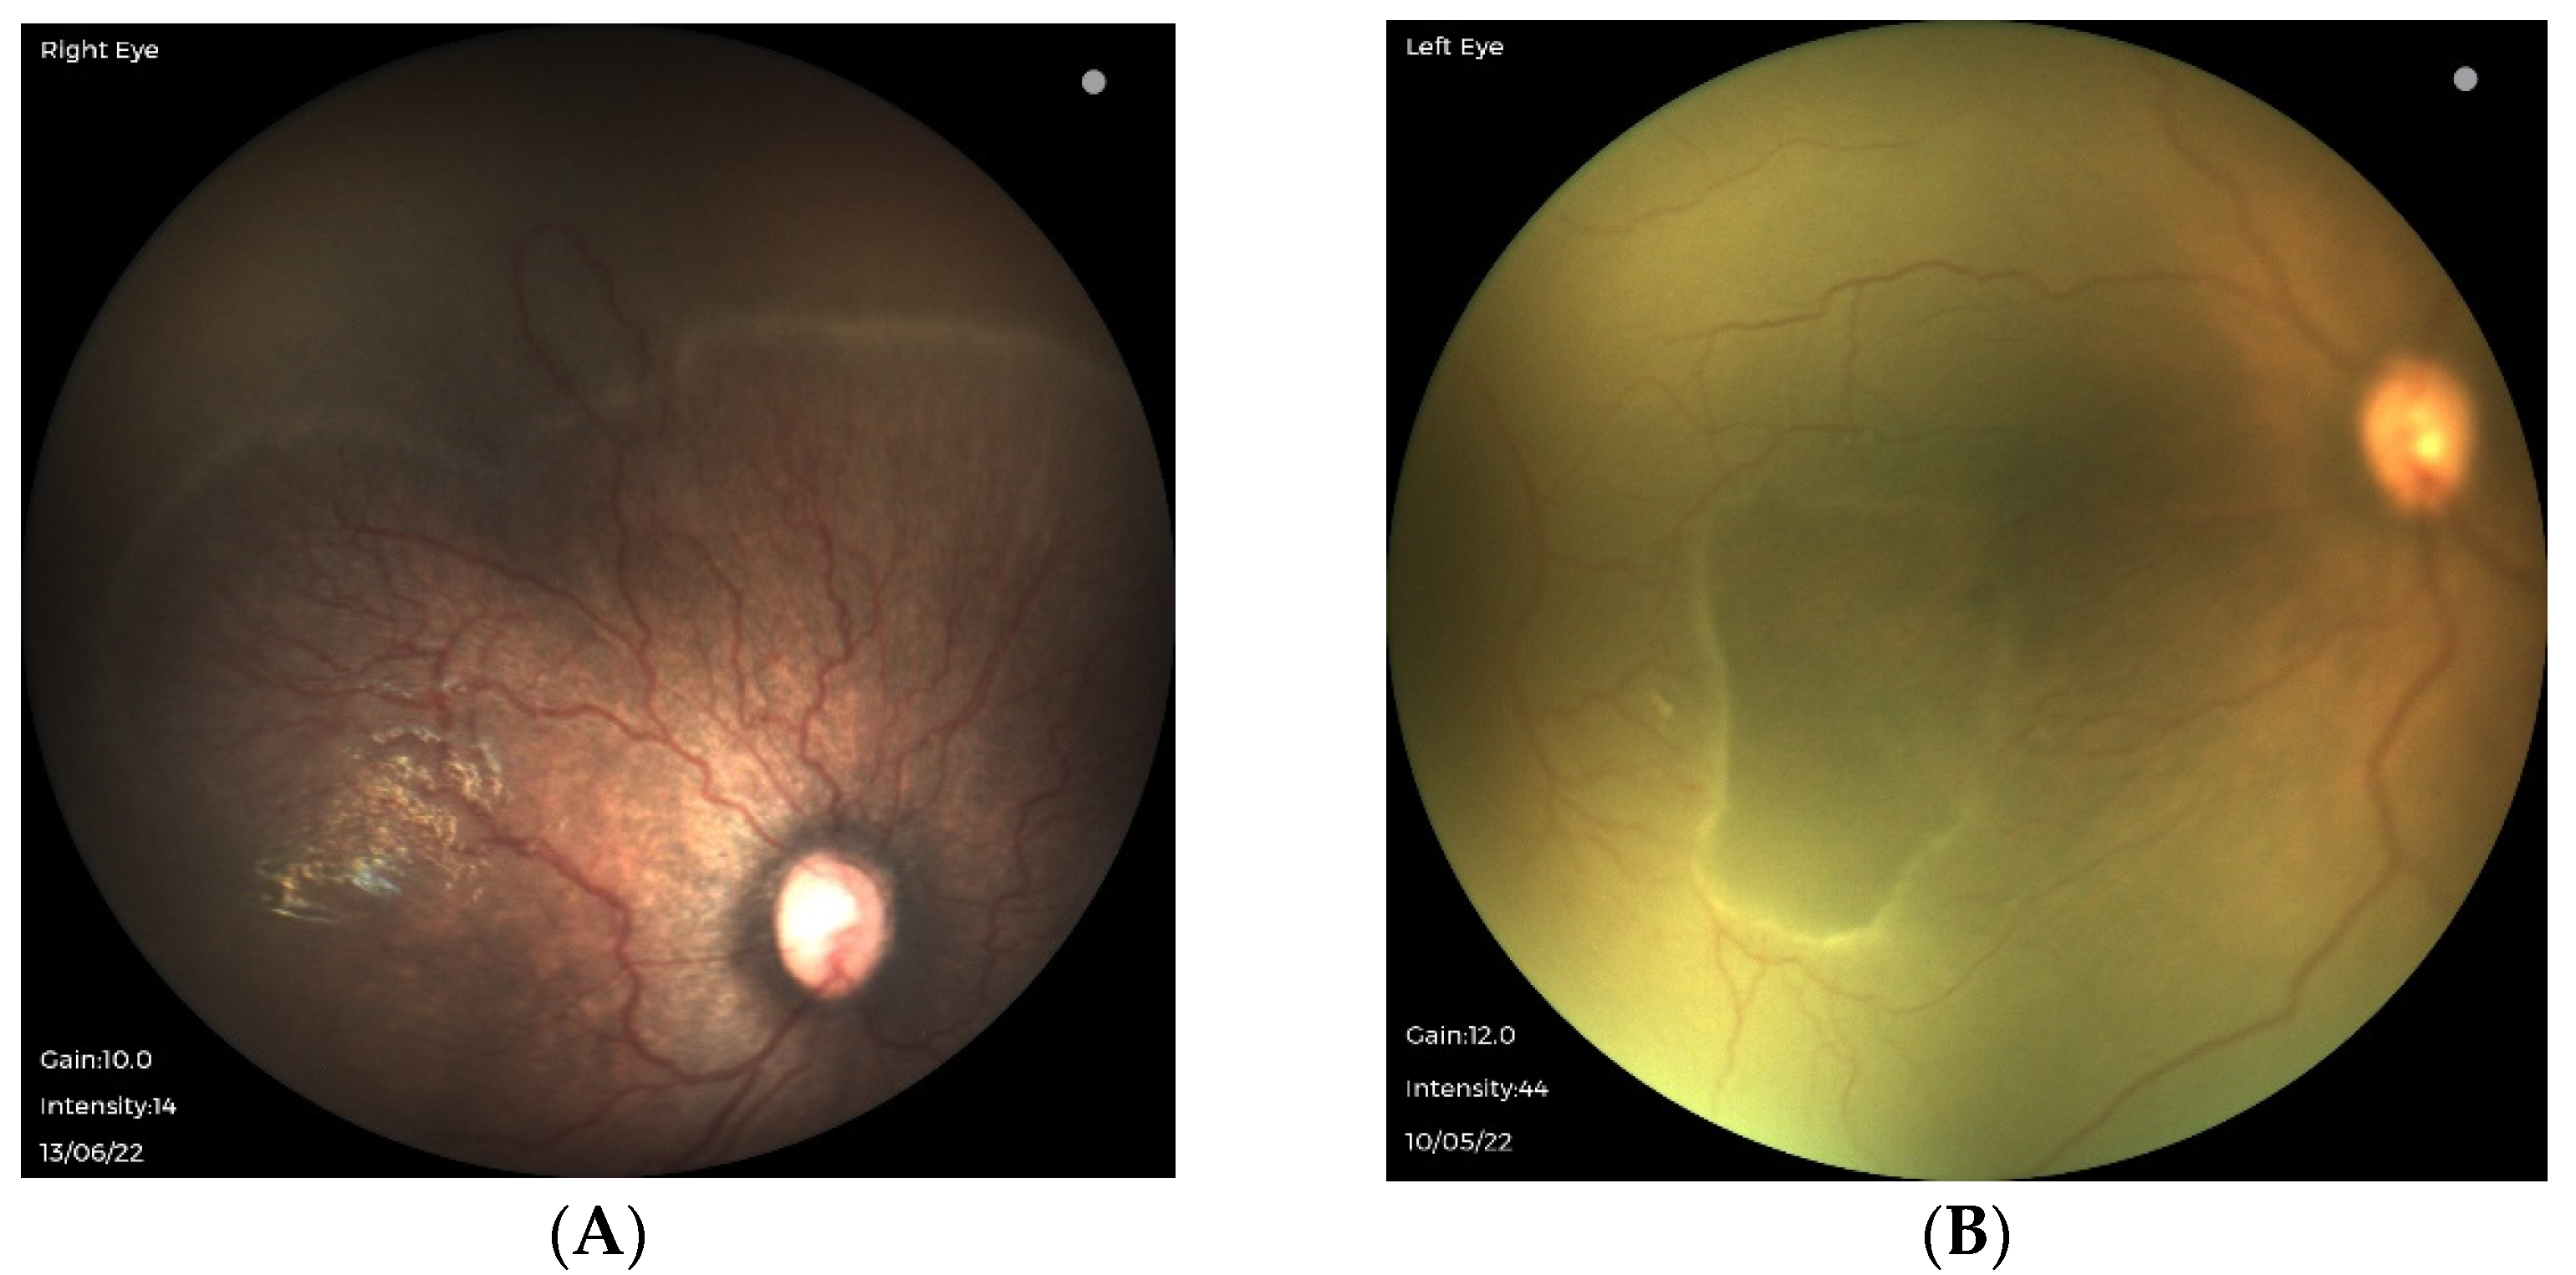

3.1. Traditional ROP in Extremely Preterm Infants with Strict Oxygen Regulation

3.2. Oxygen-Associated ROP Seen in Larger Preterm Infants